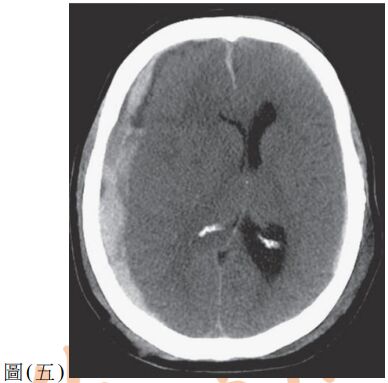

38. 一位摩托車車禍病人送至醫院,其電腦斷層顯示如圖(五),下列敘述何者最適當? (A) 外傷造成中腦膜動脈破裂出血 (B) 病人有發生大腦疝脫情形 (C) 病人症狀為左側上下肢體偏癱 (D) 電腦斷層所見屬於急性硬腦膜下出血